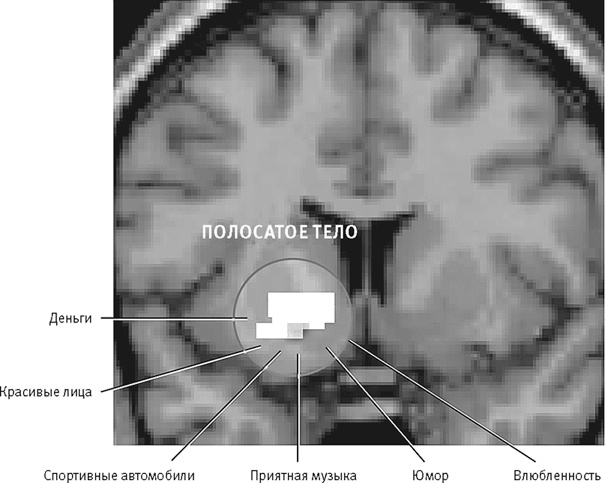

Как можно было предположить, вещества, усиливающие или продлевающие естественное действие дофамина, приносят нам большее удовольствие. Зависимость, вызываемая рядом психотропных веществ, например кокаином или амфетамином, связана именно с тем, что они сбивают с толку дофаминергическую систему, заставляя мозг думать, будто он получает награду, хотя никакой награды нет (рис. 26–4).

Система удовольствия мозга активируется и тогда, когда мы наслаждаемся произведением искусства, или любуемся закатом, или смакуем вкусный обед, или занимаемся сексом. Во всех перечисленных случаях наши ощущения отнюдь не ограничиваются восходящими процессами выделения дофамина, а включают, как мы убедимся, и нисходящие процессы, связывающие данный опыт с предшествующим, в том числе с испытанными ранее удовольствиями. Восприятие произведений искусства и других объектов эстетического наслаждения, как и вообще приятные эмоциональные реакции, включает не только непосредственное действие физического стимула, но и запускаемую им последовательность бессознательных умозаключений, порождающих контекст, в котором мы его воспринимаем.

Рис. 26–4. Дофаминергические нейроны полосатого тела реагируют на всевозможные стимулы, доставляющие нам удовольствие.